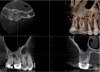

Figure 14 and Figure 15 show the preoperative digital images for another case with a necrotic pulp. In the preoperative 3D CBCT volume, the clinician observed that the mesiobuccal system, distobuccal system, and palatal system all communicated. On evaluating the mesiobuccal system, the clinician observed anastomoses between the canals. The clinician sought to employ a conservative approach to treating the case. Figure 16 and Figure 17 show the postoperative scans wherein it can be seen that the clinician practiced "directed dentin conservation" (a term attributed to Dr. David Clark and Dr. John Khademi and perpetuated by Dr. Eric Herbranson).12 The only mechanical objective not illustrated by this case is the continuous tapering preparation. Overall, the original root canal system anatomy was maintained and the foramen was kept as small as practical. Figure 18 shows an inverted postoperative radiograph that better illustrates both of these principles.

Fig 14. Preoperative radiographic image (Fig 14), preoperative CBCT (Fig 15), postoperative scans (Fig 16 and Fig 17), and inverted postoperative image (Fig 18).

Figure 14

Fig 15. Preoperative radiographic image (Fig 14), preoperative CBCT (Fig 15), postoperative scans (Fig 16 and Fig 17), and inverted postoperative image (Fig 18).

Figure 15

Fig 16. Preoperative radiographic image (Fig 14), preoperative CBCT (Fig 15), postoperative scans (Fig 16 and Fig 17), and inverted postoperative image (Fig 18).

Figure 16

Fig 17. Preoperative radiographic image (Fig 14), preoperative CBCT (Fig 15), postoperative scans (Fig 16 and Fig 17), and inverted postoperative image (Fig 18).

Figure 17

Fig 18. Preoperative radiographic image (Fig 14), preoperative CBCT (Fig 15), postoperative scans (Fig 16 and Fig 17), and inverted postoperative image (Fig 18).

Figure 18